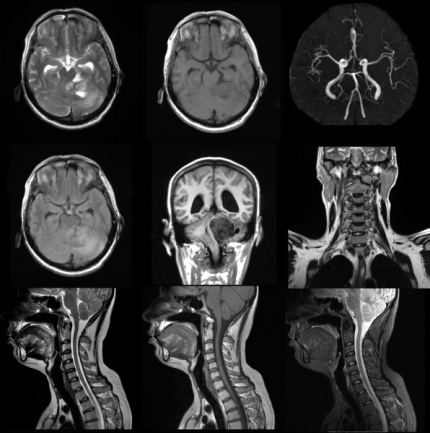

奥泰医疗1.5T MRI 图像质量反馈

头部和颈椎图像